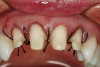

For an esthetic gingival display, it is critical that symmetry (right and left) exists as far as cervicoincisal tooth height and gingival zenith positions are concerned. Patients who exhibit asymmetrical gingival levels may be candidates for surgical gingival and/or alveolar bone repositioning to improve their esthetics (Figure 1). Typically, these patients have adequate amounts of attached gingiva so that, after the resective procedure, the mucogingival junction will not be encroached upon. If adequate amounts of free gingiva exist, minor asymmetries can be corrected with gingivectomy or gingivoplasty alone. A minimum sulcus depth of 1 mm must always remain after any tissue resection unless the alveolar bony crest is also repositioned in the apical direction as well. To give the appearance of spatially moving teeth in the cervical direction to alleviate excessive gingival display or asymmetry, osseous correction must often be peformed in conjunction with soft-tissue resection because of sulcus depth violation. A tissue marker can be used to plan the soft-tissue surgery (Figure 2). Following the guidelines for esthetic tissue levels, the perceived final gingival level is traced, creating heights of contour at the distolabial line angles. The Er,Cr:YSGG laser was used to remove the gingival tissue and create symmetry according to the proposed surgical plan (Figure 3).

Figure 2  A black marker was used to delineate the surgical plan. The patient had chosen to treat only tooth Nos. 7 through 10. The tissue level over tooth No. 8 needed to be positioned more apically to be symmetrical with tooth No. 9. The gingival level above tooth No. 10 also needed to be raised slightly to better match the tissue level of tooth No. 7.

Figure 2

Figure 3  A gingivectomy was performed using an Er,Cr:YSGG laser to harmonize the soft-tissue levels. Biologic width was encroached upon and, therefore, a repositioning of the bony crest was also needed to prevent a relapse of the preoperative tissue position.

Figure 3